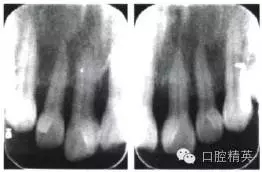

根尖片示:211牙根長度尚可,牙槽骨水平吸收約占根長1/2,根尖周未見明顯異常(圖2)。牙周檢查表見圖3。診斷:慢性牙周炎;211牙齦退縮+齦乳頭缺失;上下頜牙列缺損;錯牙合畸形。

圖2 初診時上前牙根尖片